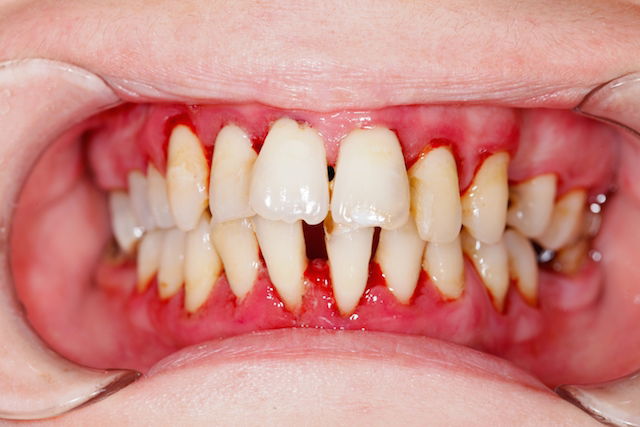

Sabe quando a gengiva fica inchada, vermelha e sangra fácil? Se isso já virou rotina, é sinal de gengivite crônica. E olha, ignorar isso só piora o quadro. Muita gente acha que é normal, mas não é. Se você não cuidar, a inflamação pode avançar e virar algo mais sério, como periodontite. Essa é a fase em que o osso que segura seus dentes começa a ser afetado. Ninguém quer chegar nesse ponto, né?

Vamos falar sério agora sobre gengivite crônica. Se você sente que já tentou de tudo em casa e a coisa não melhora, é hora de ligar o alerta. Ignorar a gengivite crônica pode levar a problemas maiores, como a periodontite, que afeta o osso que segura seus dentes. Pois é, a situação pode ficar mais complicada se a gente não der a devida atenção.

A gengivite crônica se caracteriza por uma inflamação persistente na gengiva, que fica vermelha, inchada e pode até sangrar com facilidade. Muitas vezes, a causa é o acúmulo de placa bacteriana que não foi removida corretamente com a escovação e o fio dental. Quando ela se torna crônica, os cuidados caseiros podem não ser suficientes para reverter o quadro, e a ajuda profissional se torna indispensável.

Se você está nessa situação, o melhor caminho é procurar um dentista. Ele poderá avaliar a extensão do problema, fazer uma limpeza profissional mais profunda (raspagem) para remover a placa e o tártaro acumulados, e indicar o tratamento mais adequado para o seu caso. Fique tranquila, o dentista está ali para te ajudar a reconquistar a saúde bucal.

| Quando a Ajuda Profissional é Essencial | Sangramento persistente, inchaço acentuado, dor forte, mau hálito crônico, retração geng |

Sim, pode. Se não tratada, a gengivite crônica pode evoluir para periodontite, uma doença mais séria que afeta os ossos e tecidos que sustentam os dentes. Isso pode levar à perda dentária.